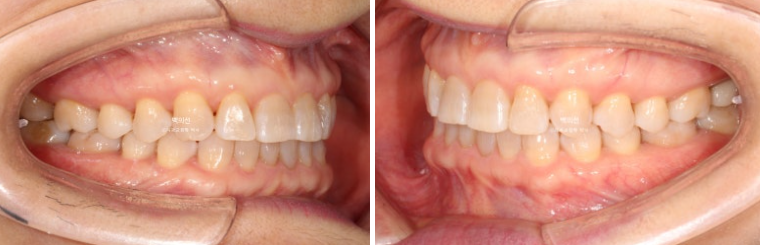

25.02~25.08

인비절라인 익스프레스로 과개교합 개선이 가능합니다.

앞니 교합이 얕아지면서 윗니에 가려 잘 안 보이던 아래 앞니가 이제 절반 이상 보이게 되었습니다.

레진으로 메꿔놓았던 틈은 교정으로 완벽하게 사라졌습니다.

앞니 뿐 아니라 송곳니가 튀어나왔던 부분도 배열이 개선이 되었습니다.